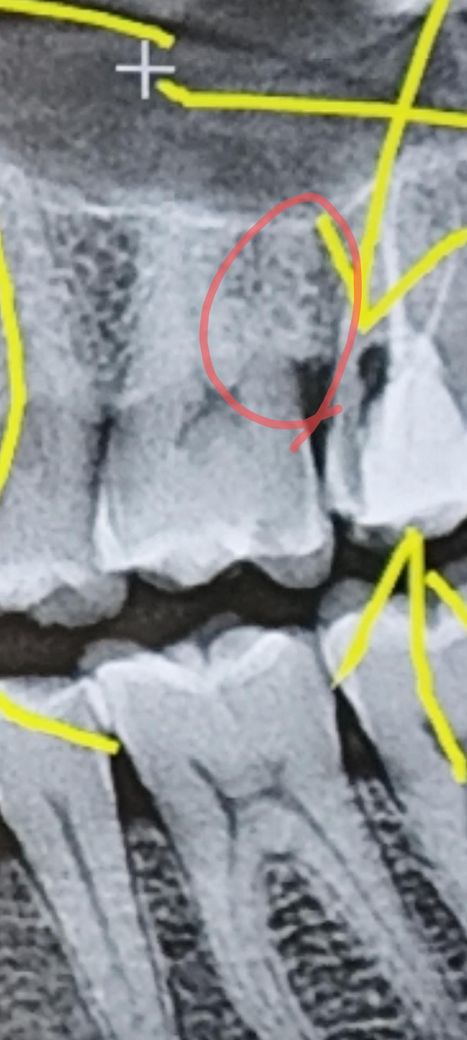

뿌리에 금간거 같은데 치아균열 일수도있나요?

빨간동그라미친 부위가 치간칫솔이 들어가면 찌릿찌릿

하고 아픈데 충치나 뿌리균열 일까요?

치아상태가 괜찬은건지 한번 사진 봐주시면 감사합니다

빨간 원 내의 검은 줄은 크랙이 아니고 치아 속의 신경 주행입니다. 치아와 관련된 문제보다는 잇몸 염증 때문에 나타날 수 있는 증상같습니다.